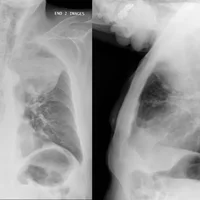

Diagnostic : le diagnostic de la pneumonie peut être posé à l'aide de plusieurs méthodes, notamment :

• Radiographie thoracique pour visualiser les zones affectées des poumons.